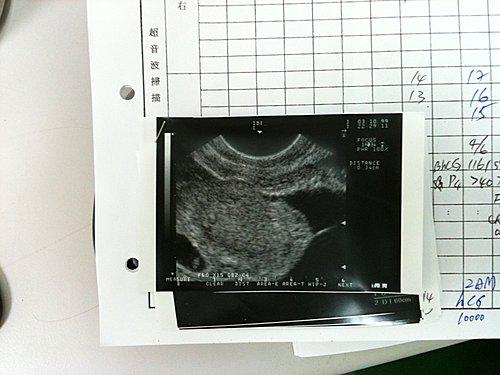

I went to the clinic for the first time on March 10th, took 6 injections; went there for the second time on March 15th and took 2 injections; and the third time Dr. Chang told me to do COH on March 19th, so I had to go back to take HCG. The fourth time on March 19th, I only obtained 3 ova (probably my ova began to age, but Dr. Chang comforted me and said even if there was only one healthy ova, there was still a chance to success). The fifth time on March 22nd, I did the implantation and took some progesterone home (a little bit painful). April 6th was the day to reveal the result, and it turned out that I really got pregnant. I never had such luck to achieve success at one time. This was the completely new day for both my husband and I, because we had been looking forward every month for the past ten years, but only failed again and again.